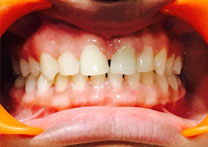

(4) Diastema Closure

Before Treatment

After Treatment

Patient with a complaint of a gap in between upper central incisors. Dental Veneers done to close the gap between the central incisors